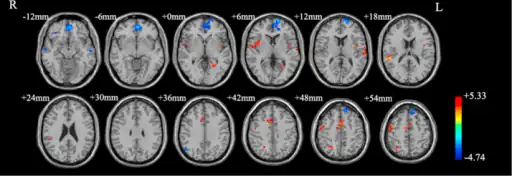

Functional neuroimaging during symptom provocation has observed abnormal activity in the orbitofrontal cortex, left dorsolateral prefrontal cortex, right premotor cortex, left superior temporal gyrus, globus pallidus externus, hippocampus and right uncus. Weaker foci of abnormal activity were found in the left caudate, posterior cingulate cortex and superior parietal lobule.[61] However, an older meta analysis of functional neuroimaging in OCD reported the only consistent functional neuroimaging findings have been increased activity in the orbital gyrus and head of the caudate nucleus, while ACC activation abnormalities were too inconsistent.[62] A meta analysis comparing affective and non affective tasks observed differences with controls in regions implicated in salience, habit, goal-directed behavior, self-referential thinking and cognitive control. For non affective tasks, hyperactivity was observed in the insula, ACC, and head of the caudate/putamen, while hypoactivity was observed in the medial prefrontal cortex (mPFC) and posterior caudate. Affective tasks were observed to relate to increased activation in the precuneus and posterior cingulate cortex(PCC), while decreased activation was found in the pallidum, ventral anterior thalamus and posterior caudate.[63] The involvement of the cortico-striato-thalamo-cortical loop in OCD as well as the high rates of comorbidity between OCD and ADHD have led some to draw a link in their mechanism. Observed similarities include dysfunction of the anterior cingulate cortex, and prefrontal cortex, as well as shared deficits in executive functions.[64] The involvement of the orbitofrontal cortex and dorsolateral prefrontal cortex in OCD is shared with bipolar disorder and may explain their high degree of comorbidity.[65] Decreased volumes of the dorsolateral prefrontal cortex related to executive function has also been observed in OCD.[66]

People with OCD evince increased grey matter volumes in bilateral lenticular nuclei, extending to the caudate nuclei, with decreased grey matter volumes in bilateral dorsal medial frontal/anterior cingulate gyri.[67][68] These findings contrast with those in people with other anxiety disorders, who evince decreased (rather than increased) grey matter volumes in bilateral lenticular / caudate nuclei, as well as decreased grey matter volumes in bilateral dorsal medial frontal/anterior cingulate gyri.[68] Increased white matter volume and decreased fractional anisotropy in anterior midline tracts has been observed in OCD, possibly indicating increased fiber crossings.[69]

Brain regions showing different functional connectivity between obsessive–compulsive disorders and controls

Brain regions showing different functional connectivity between obsessive–compulsive disorders and controls -